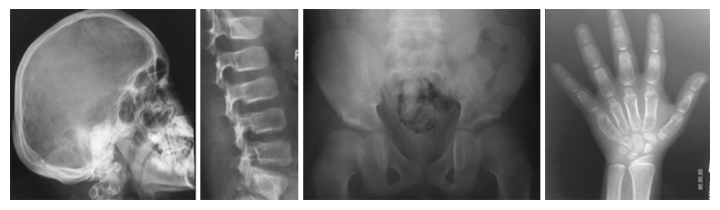

新たなタイプの骨の難病、Ikegawa型頭蓋管状骨異形成症のレントゲン像

また、運動器の遺伝性難病の医療と研究のために「骨系統疾患コンソーシウム」を設立し注2)、骨格、運動器の遺伝性難病の臨床データを世界中から収集してきました。その中に、共通の骨格異常を持つ4家系5人の患者を発見しました。これらの患者には、頭蓋骨の骨濃度の上昇、脊椎の形成異常、長管骨と短管骨の骨幹部の拡大などの特徴的な異常が認められました(図1)。このような骨格異常の組み合わせは過去に報告がなく、新たな疾患として「Ikegawa型頭蓋管状骨異形成症(Craniotubular dysplasia, Ikegawa type)」と名付けました。

図1 Ikegawa型頭蓋管状異形成症の表現型

頭蓋骨と管状骨(長管骨、短管骨)の肥厚、骨濃度の上昇などの特徴が見られる。

- 1前額部突出、眼間距離の拡大など特徴的な顔貌。

- 2-5特徴的なX線像。2肥厚した頭蓋骨、3脊椎椎体の扁平化、4大腿骨骨幹端部の短縮、5手の短管骨の骨幹部の拡大。